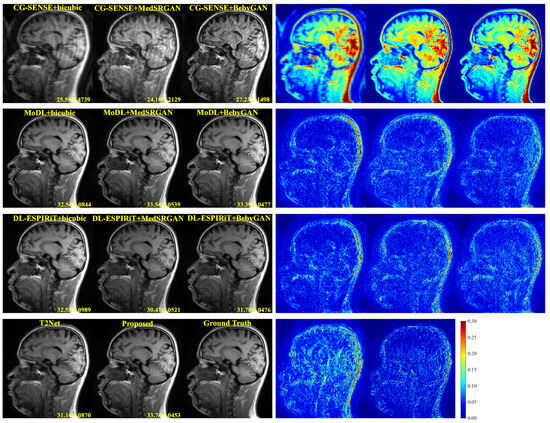

To comprehensively evaluate the performance of our proposed model, we conducted a series of comparison experiments on the two datasets. Specifically, we compared our method with ten other models, which include nine Recon+SR methods and one state-of-the-art multi-task method called T2Net [56]. For the nine Recon+SR methods, we selected three reconstruction algorithms (CG-SENSE [57], MoDL [16], and DL-ESPIRiT [20]) and three super-resolution algorithms (bicubic, MedSRGAN [44], and BebyGAN [34]). These algorithms were combined sequentially to form the nine comparison methods. To ensure a fair comparison, each of these methods was carefully optimized to guarantee the best performance and ensure equitable evaluations.

For a more intuitive comparison, we provide visual comparisons for each method. In Figure 5 and Figure 6, we illustrate the axial and sagittal views of the 2D brain dataset, respectively. In Figure 7 and Figure 8, we display the brain image and neck image of the 3D VWI dataset. For each method, we show the restorations along with the corresponding error maps. The images are placed on the left, the error maps on the right, and the PSNR and LPIPS metrics of each image are shown at the bottom right corner. From the error maps, it is evident that our proposed method consistently produces high-quality results with improved visual fidelity and better retention of structural information compared to the other methods.

Figure 6. Visual comparison of each method for a slice of sagittal view in the brain dataset.